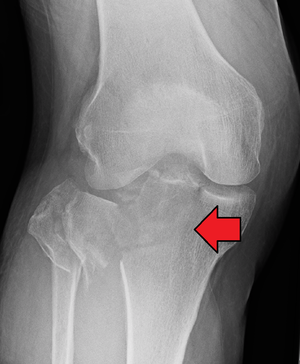

Диагностика разрыва ПКС

Составляющие диагностики при подозрении на разрыв передней крестообразной связки:

- рентген – в остром периоде травмы;